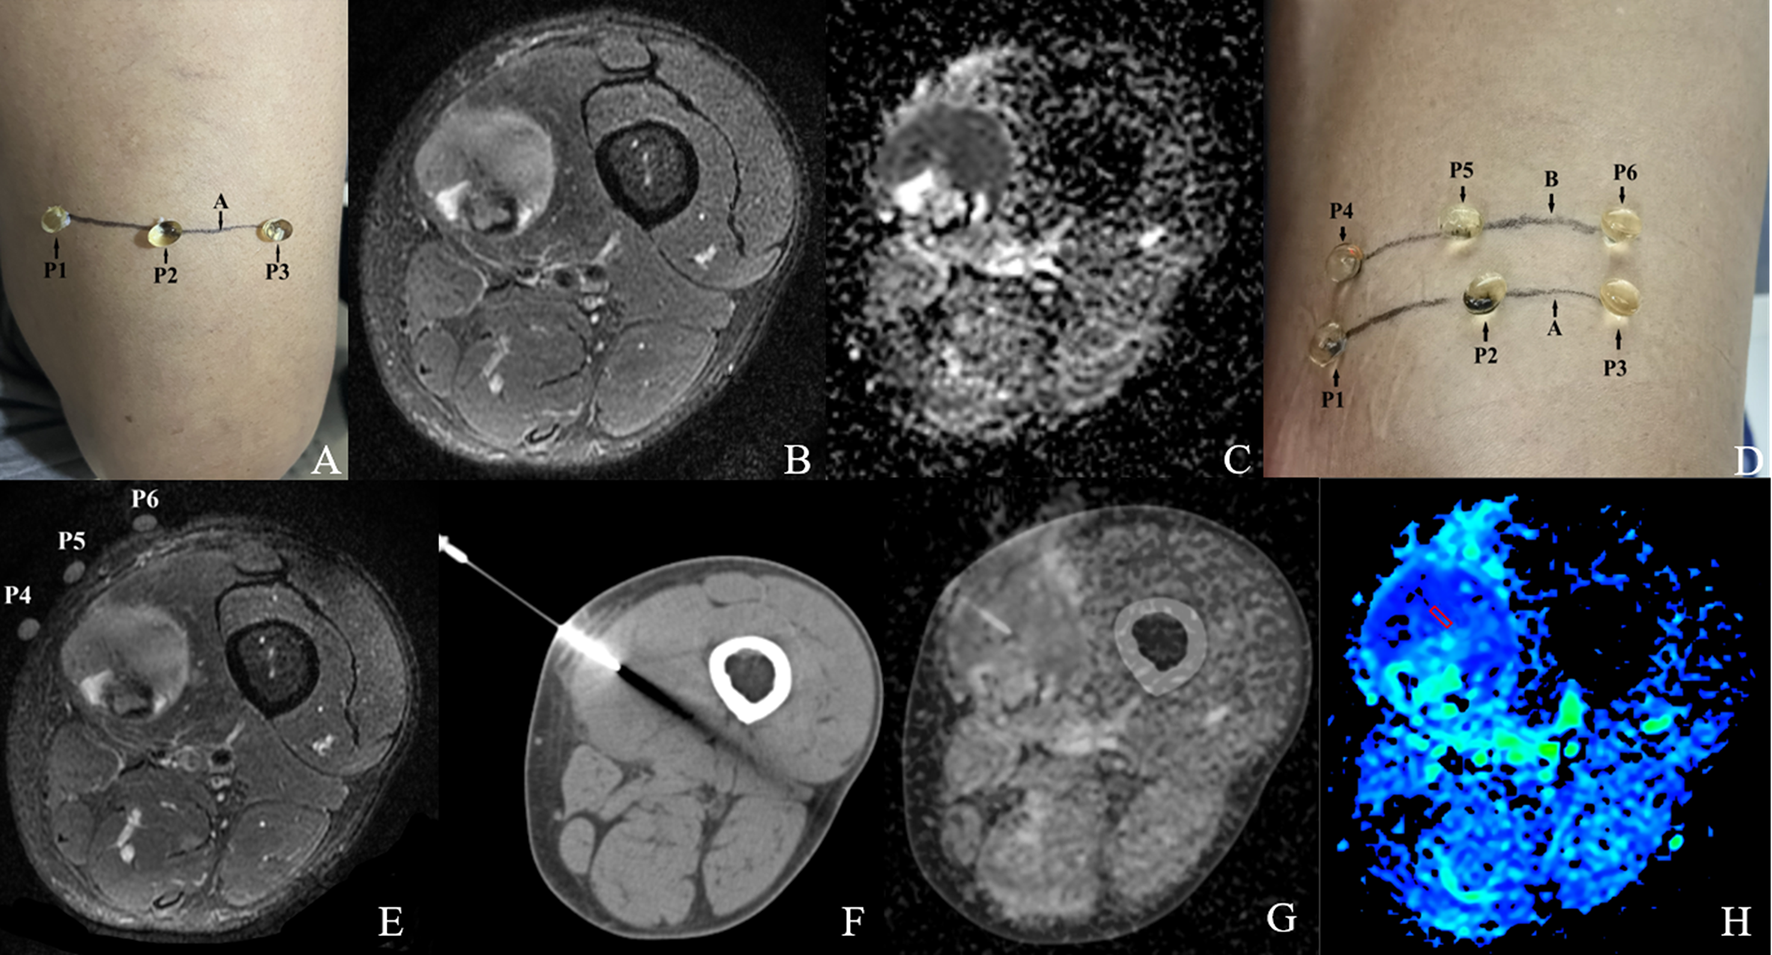

Figures 4 and 5 show the features of the CT-MR fusion registration images, pathological diagnosis, and Ki-67 LI images of the histologically confirmed pleomorphic leiomyosarcomas and myxofibrosarcomas.

Figure 5. Male,35Y, Myxofibrosarcoma of the right calf, G1. (A) Body surface positioning marks before MRI examination; (B, C) Targeted slice, chosen by Axial T2WI-FS and ADC image; (D) CT guided biopsy at target slice; (E) CT-MRI image fusion at target slice; (F) Draw ROI to obtain DWI quantitative parameters, ADCmin: 3.280×10–3 mm2/s, ADCmean: 3.370×10–3 mm2/s; (G) 1H MR spectrum, Cho/Cr:2.25; (H) Histological images of biopsy specimens, Grade3, HE×200; (I) Ki67 index 10%.